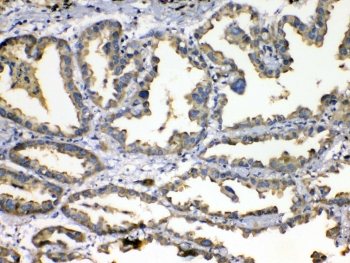

IHC testing of FFPE human lung cancer tissue with SOD3 antibody at 1ug/ml. Required HIER: steam section in pH6 citrate buffer for 20 min and allow to cool prior to testing.